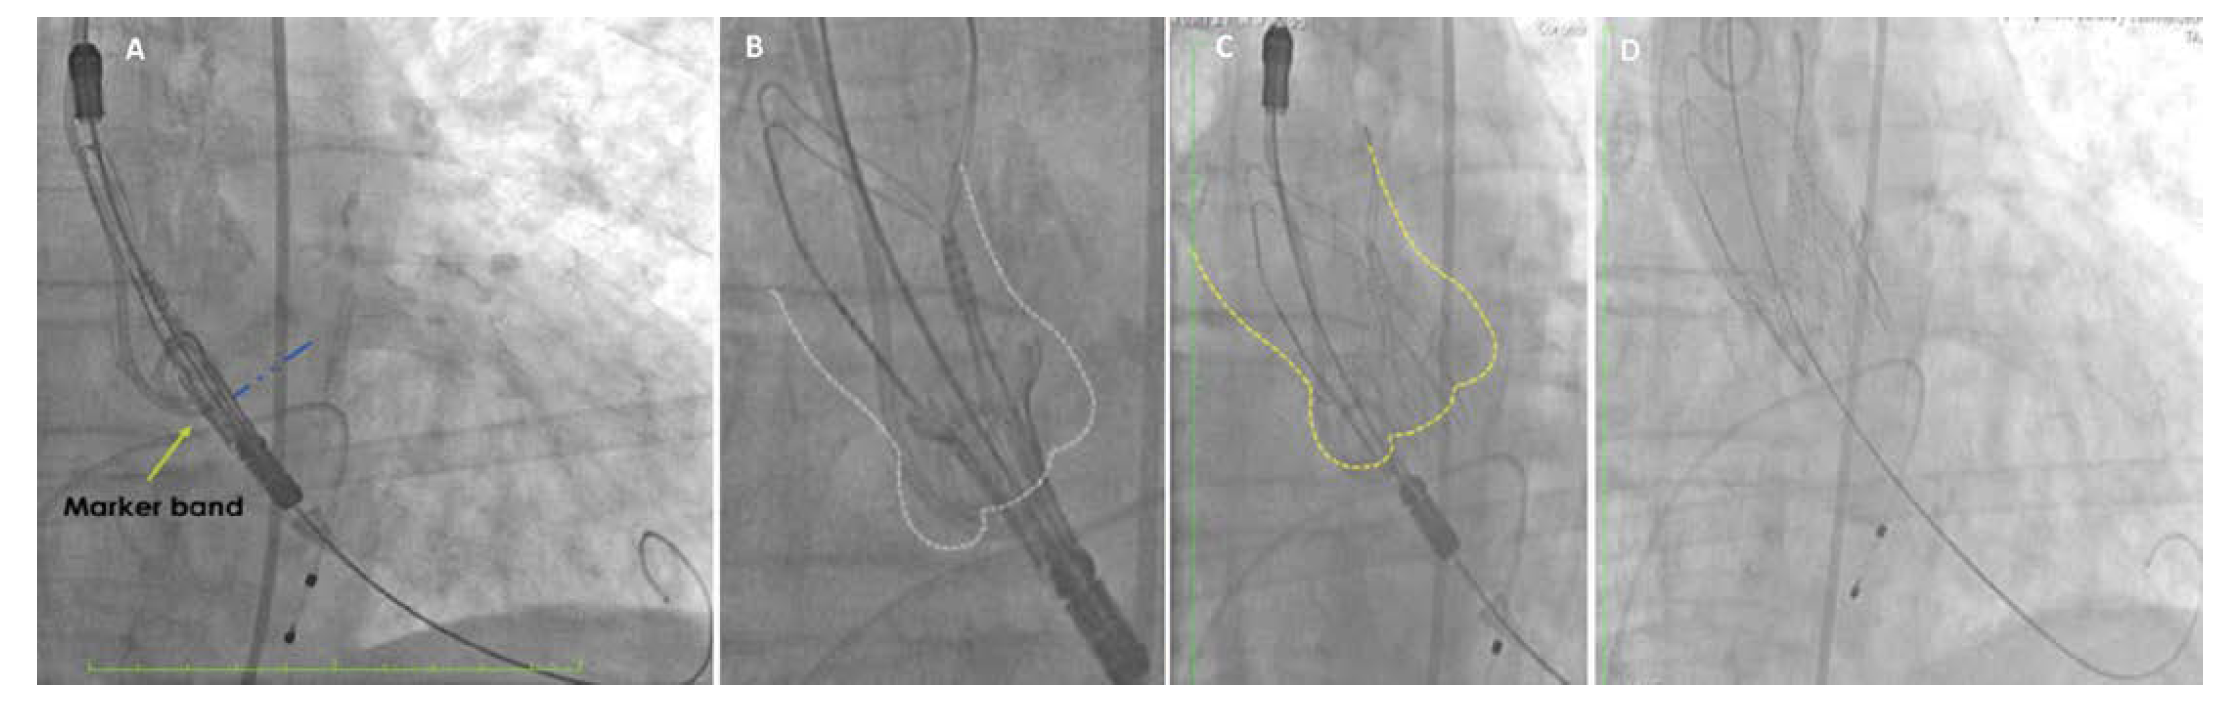

The Symetis Acurate TF delivery system (Boston Scientific) navigated easily through the introducer sheath and aortic arch, and, once positioned, oriented itself to the outer curvature of the ascending aorta (Figure 4A). When the marker band was well aligned on the virtual basal ring, we started with the top-down deployment (Figures 4B/C). Here it was crucial to handle the Acurate TF Delivery System only on the positioning sheath to avoid any unintentional movement that might have led to an uneven deployment of the prosthesis (Figure 5). The release of the Acurate neo (medium size) was as uncomplicated and straightforward as for the transfemoral approach, and after deployment, the Acurate TF delivery system could be easily removed. Angiography showed a good positioning of the prosthesis with trivial paravalvular leak (Figure 4D). Pressure measurements in the aorta and in the left ventricle did not show any gradient, and the subclavian artery was closed with sutures. The previously prepared purse string facilitated the removal of the delivery system from the subclavian artery and the final closure of the vessel with sutures.

The final results were good. As shown in Figure 4D, the lower crown of the Acurate neo valve protrudes only minimally into the left ventricular outflow tract. Accordingly, we did not observe any conduction disturbance despite baseline right bundle branch block and left anterior hemiblock.